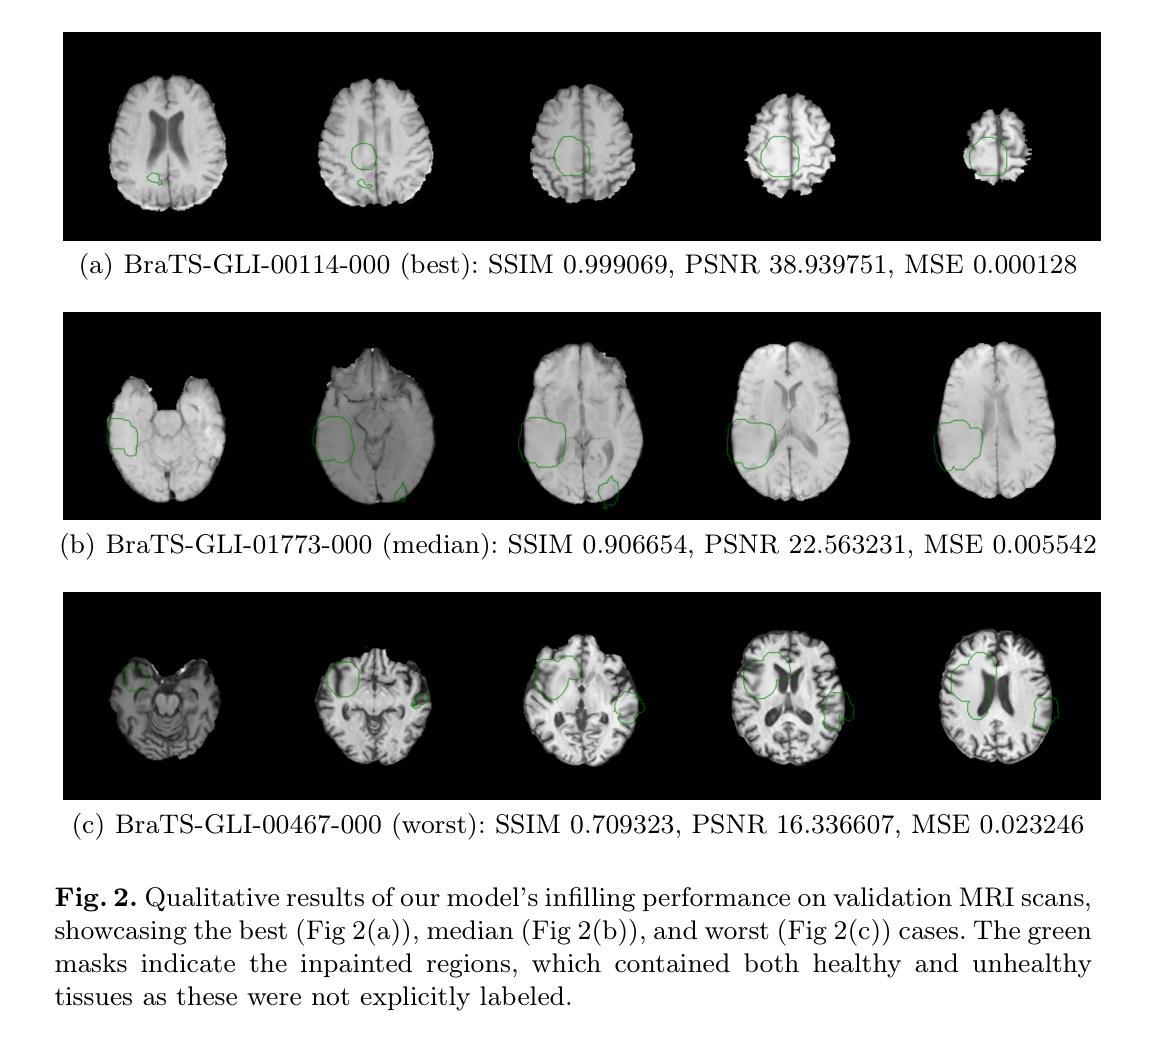

The ASNR-MICCAI BraTS-Inpainting Challenge was established to mitigate dataset biases that limit deep learning models in the quantitative analysis of brain tumor MRI. This paper details our submission to the 2025 challenge, a novel deep learning framework for synthesizing healthy tissue in 3D scans. The core of our method is a U-Net architecture trained to inpaint synthetically corrupted regions, enhanced with a random masking augmentation strategy to improve generalization. Quantitative evaluation confirmed the efficacy of our approach, yielding an SSIM of 0.873$\pm$0.004, a PSNR of 24.996$\pm$4.694, and an MSE of 0.005$\pm$0.087 on the validation set. On the final online test set, our method achieved an SSIM of 0.919$\pm$0.088, a PSNR of 26.932$\pm$5.057, and an RMSE of 0.052$\pm$0.026. This performance secured first place in the BraTS-Inpainting 2025 challenge and surpassed the winning solutions from the 2023 and 2024 competitions on the official leaderboard.

ASNR-MICCAI BraTS-Inpainting挑战赛旨在减轻数据集偏见,这些偏见限制了深度学习模型在脑部肿瘤MRI定量分析中的应用。这篇论文详细描述了我们对2025年挑战赛的提交内容,即一种用于在3D扫描中合成健康组织的新型深度学习框架。我们的方法的核心是U-Net架构,该架构经过训练可用于填充合成损坏区域,并采用随机掩膜增强策略来提高泛化能力。定量评估证实了我们方法的有效性,在验证集上,结构相似性指标(SSIM)为0.873±0.004,峰值信噪比(PSNR)为24.996±4.694,均方误差(MSE)为0.005±0.087。在最后的在线测试集上,我们的方法实现了SSIM 0.919±0.088,PSNR 26.932±5.057和均方根误差RMSE 0.052±0.026。这一表现使我们在BraTS-Inpainting 2025挑战赛中获得了第一名,并在官方排行榜上超越了2023年和2024年的获胜解决方案。

Summary

本论文提交了一项针对ASNR-MICCAI BraTS-Inpainting挑战的新型深度学习框架,旨在合成健康组织在三维扫描中的修复技术。通过训练U-Net架构来填充合成破坏区域,并使用随机掩膜增强策略提高泛化能力。定量评估证实此方法有效,在验证集和最终测试集上均取得优异成绩,获得BraTS-Inpainting 2025挑战第一名。

Key Takeaways

1. ASNR-MICCAI BraTS-Inpainting挑战旨在解决深度学习模型在脑肿瘤MRI定量分析中的数据集偏见问题。

2. 论文提出了一种新型的深度学习框架,用于合成三维扫描中的健康组织修复技术。

3. 该方法的核心是训练的U-Net架构,用于填充合成破坏区域。

4. 使用随机掩膜增强策略提高了模型的泛化能力。

5. 定量评估表明,该方法在验证集上取得了优异的性能指标,包括SSIM、PSNR和MSE。

6. 在最终测试集上,该方法性能卓越,获得BraTS-Inpainting 2025挑战第一名。